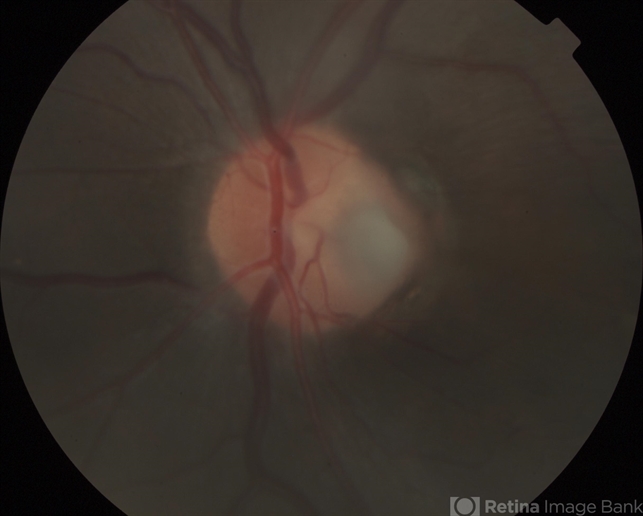

By Susanna S. Park, MD, PhD

University of California Davis Eye Center - Uploaded on Jan 9, 2014.

- optic pit

- Ellen Redeenbo, University of California Davis Eye Center

Fundus camera

Topcon - Description

- Magnfied fundus photograph of the disc showing a large optic pit on the disc.